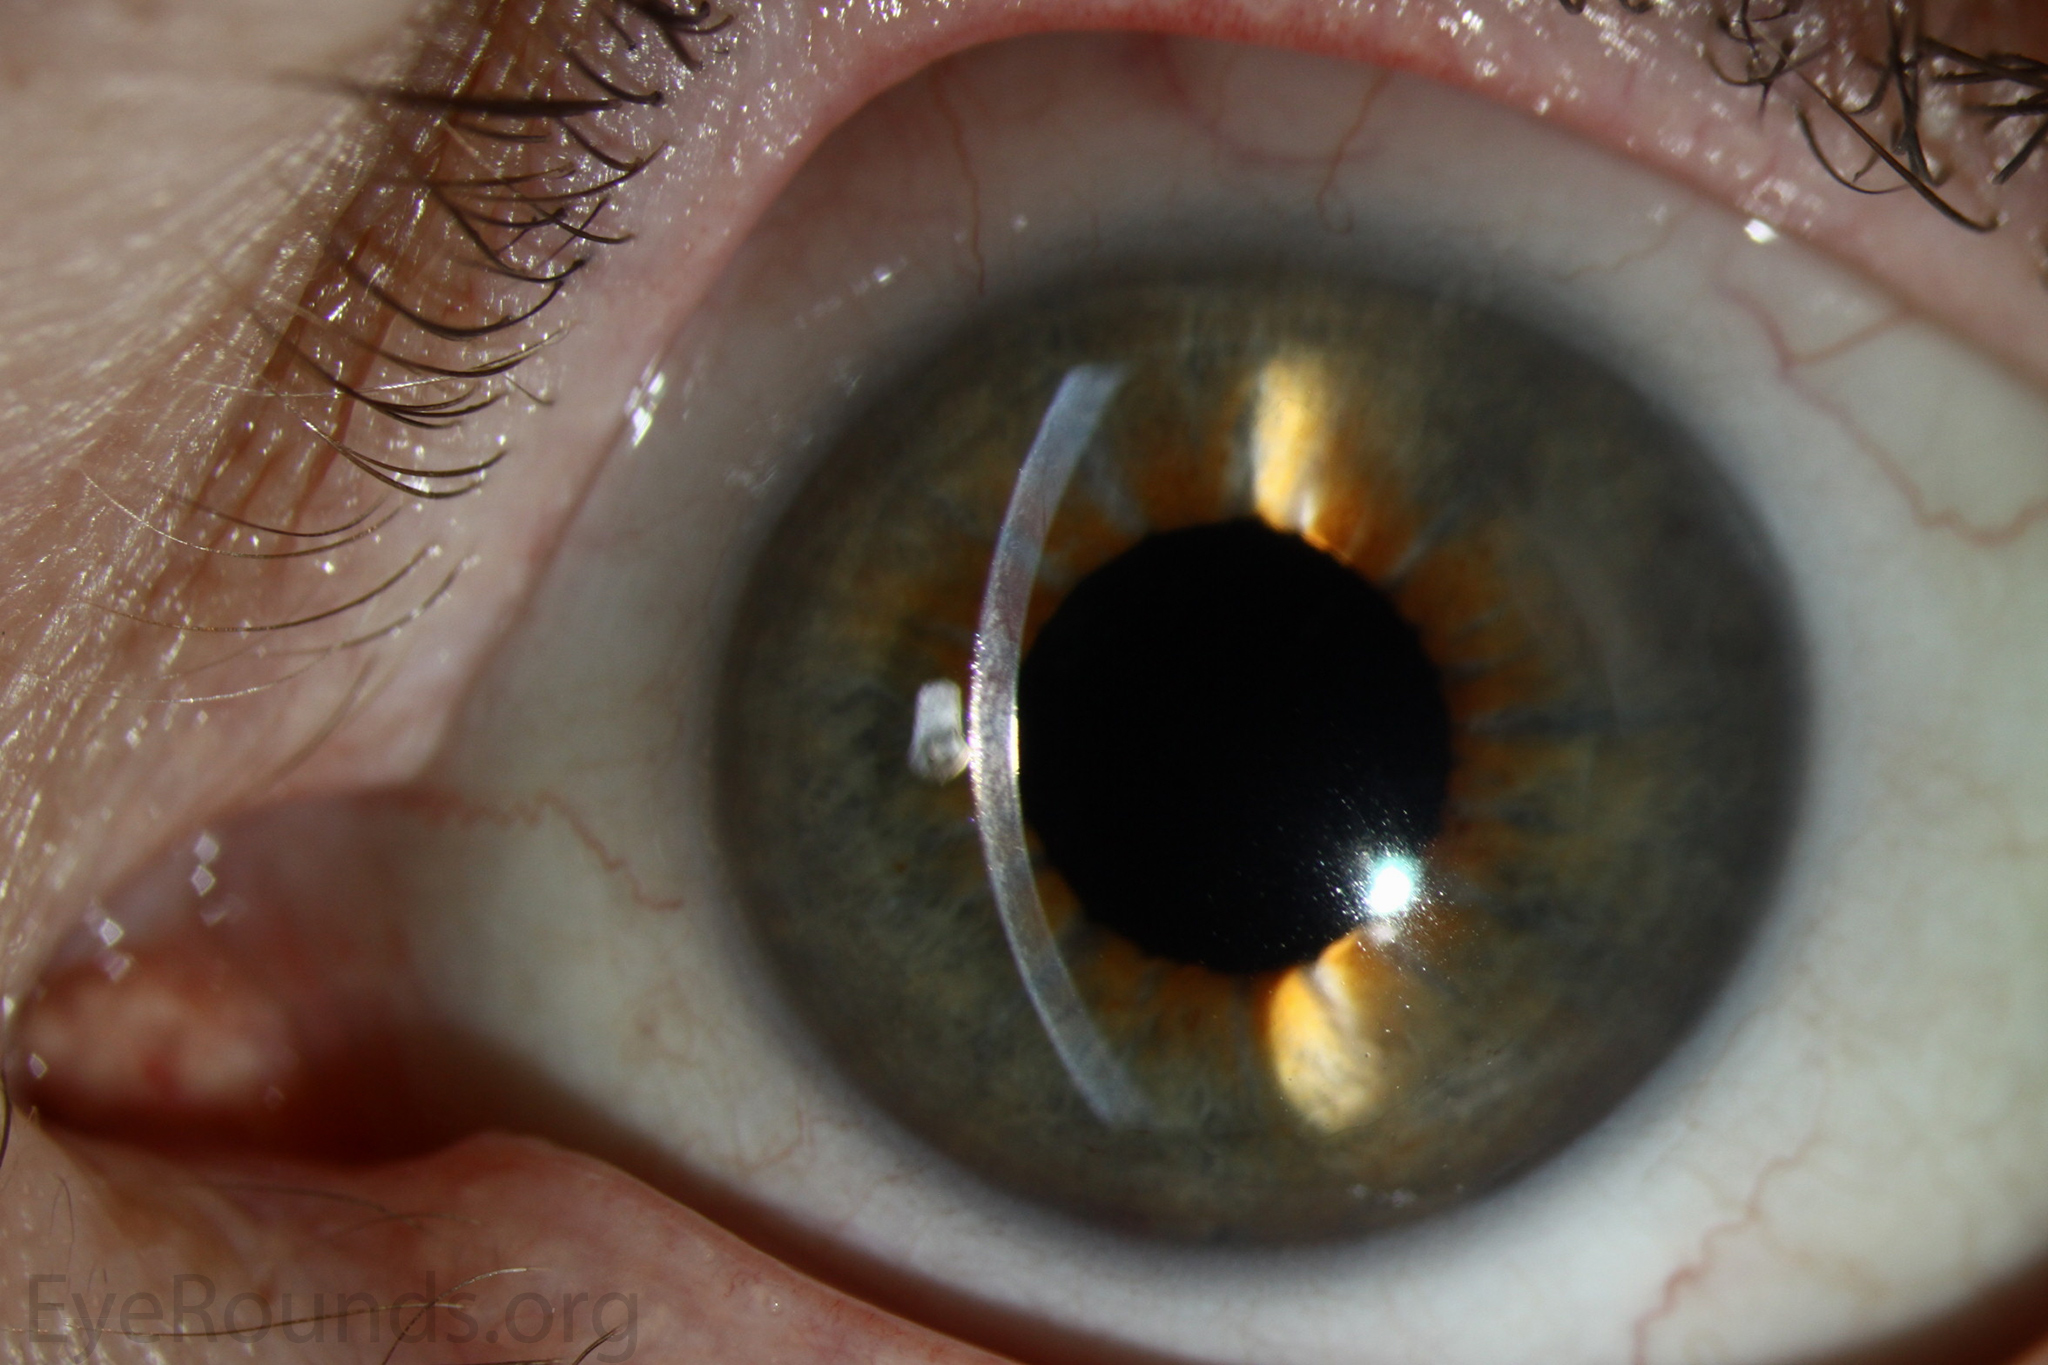

Keratoprosthesis implantation is a procedure that involves full-thickness removal of the cornea and replacement by an artificial cornea. The Boston Type I Keratoprosthesis is currently the most commonly used keratoprosthesis device in the US. It consists of a clear plastic polymethylmethacrylate (PMMA) optic and back plate sandwiched around a corneal graft and secured with a titanium locking ring (Figure 15). After the device is assembled, a partial-thickness trephination is performed on the host cornea. Full-thickness resection of the patient's cornea is then completed using curved corneal scissors. The keratoprosthesis is then secured to host tissue using interrupted or running sutures. Generally, patients who have a history of multiple failed PKs are candidates for a keratoprosthesis transplant. Other indications include severe keratitis or ocular surface disease resulting from limbal stem cell failure, such as Stevens-Johnson syndrome (Figure 16), ocular cicatricial pemphigoid, aniridia (Figure 17) and chemical injury (1, 13). The Boston Type II Keratoprosthesis is a similar device with a longer optic designed to extend through an opening made in the upper eyelid (Figure 19). It is indicated for the most severe cicatrizing ocular surface diseases.

KPro placement offers relatively fast visual rehabilitation. The devices are amenable for use in many situations in which other types of keratoplasty are not an option.

There is significant long-term risk of complications for those with a keratoprosthesis. Because the KPro is a foreign body, there is risk of infection or extrusion of the device. Post-operative glaucoma is common and intraocular pressure is difficult to evaluate as the hard optic makes traditional tonometry impossible. For this reason, glaucoma tube shunts are typically placed at the time of the corneal transplant at the University of Iowa. The Diaton is currently the preferred way to measure intraocular pressure in these patients in our institution. Patients can form retroprosthetic membranes requiring treatment with a Nd:YAG laser or surgical membranectomy (21).